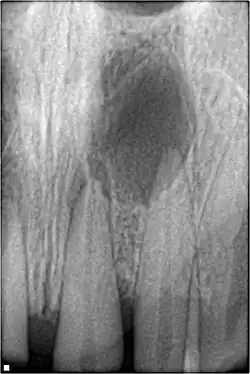

Obliteração pulpar

Entre 4 e 24% dos dentes traumatizados terão alguns graus de obliteração pulpar, que é caracterizada pela perda do espaço pulpar radiograficamente, e descoloração amarela da coroa clínica. Nenhum tratamento é necessário se for assintomático. As opções de tratamento serão a extração do dente decíduo sintomático. Para dentes permanentes sintomáticos, o tratamento endodôntico costuma ser desafiador, pois a câmara pulpar é preenchida com material calcificado e a sensação de "queda" ao entrar na câmara pulpar não ocorre. [55]